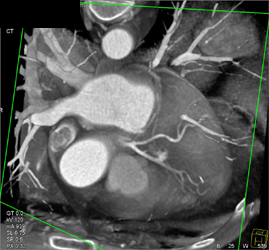

Patent Bypass Grafts